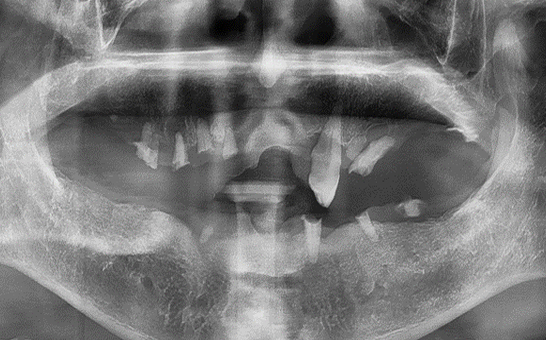

CASE 02 김** / 60대

전악임플란트

치료 시작 전 촬영 2024.01.24 | 치료 완료 후 촬영 2024.12.26

1 예후불량 치아 발치

2 발치 후 즉시 임플란트 식립 및 뼈이식

3 고정성 보철물로 수복 후 일상 회복